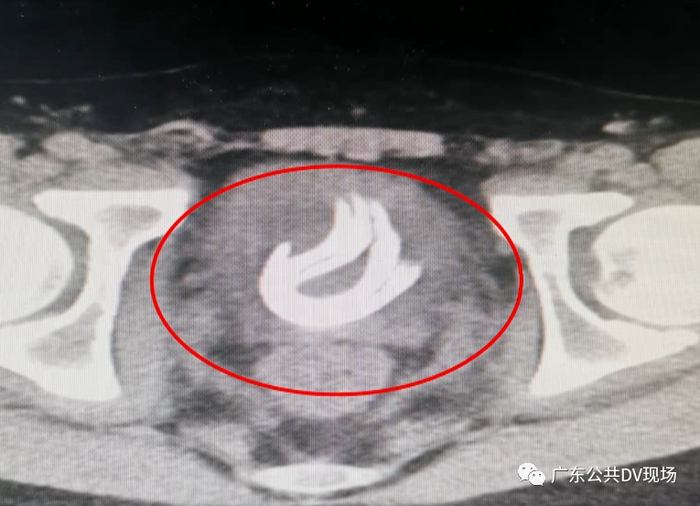

后来经X光检查

医生确实发现少年的膀胱中

有一团线圈

足足有70厘米长

更可怕的是

这团线圈已经存在少年体内

长达3个月